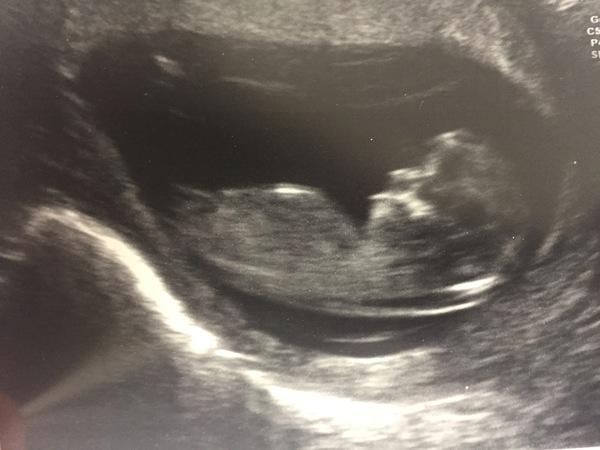

Had my 12week scan this morning.....all fine. Baby decided to kick legs around give us a little wave.

Mooseville · 22/11/2016 13:59

Scan went ok! Was pretty worried while he was doing it as he was very quiet and didn't say much.... he said at the end though, as far as he could tell from the scan all was well, but obviously you need to wait for the full blood test results. It was dancing around and he played a very brief sound of the heartbeat! (Well I think it was the babies and not mine, again he didn't say anything while doing it!!!

Nunchal measurement was 2.9. Seems quite high but I've googled and up to 3.5 is considered normal!

Oh and he put the date forward two days so 12 + 3!

Lovely scan pic! x